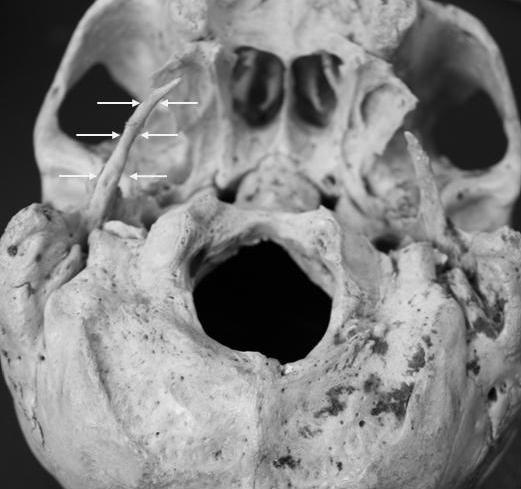

An unusual case of a unilaterally elongated styloid process with a length of 5.8 cm was found on a dry skull of a male cadaver. During his life the subject was complaining for reported ipsilateral otalgia presumably due to nerve compression from the elongated styloid process. The symptomatology appeared by such an anatomical variant as well as relative literature is discussed in this paper.

https://cdn.ncbi.nlm.nih.gov/pmc/blobs/2605/2803932/c07eb26acda8/1757-1626-2-9135-1.jpg